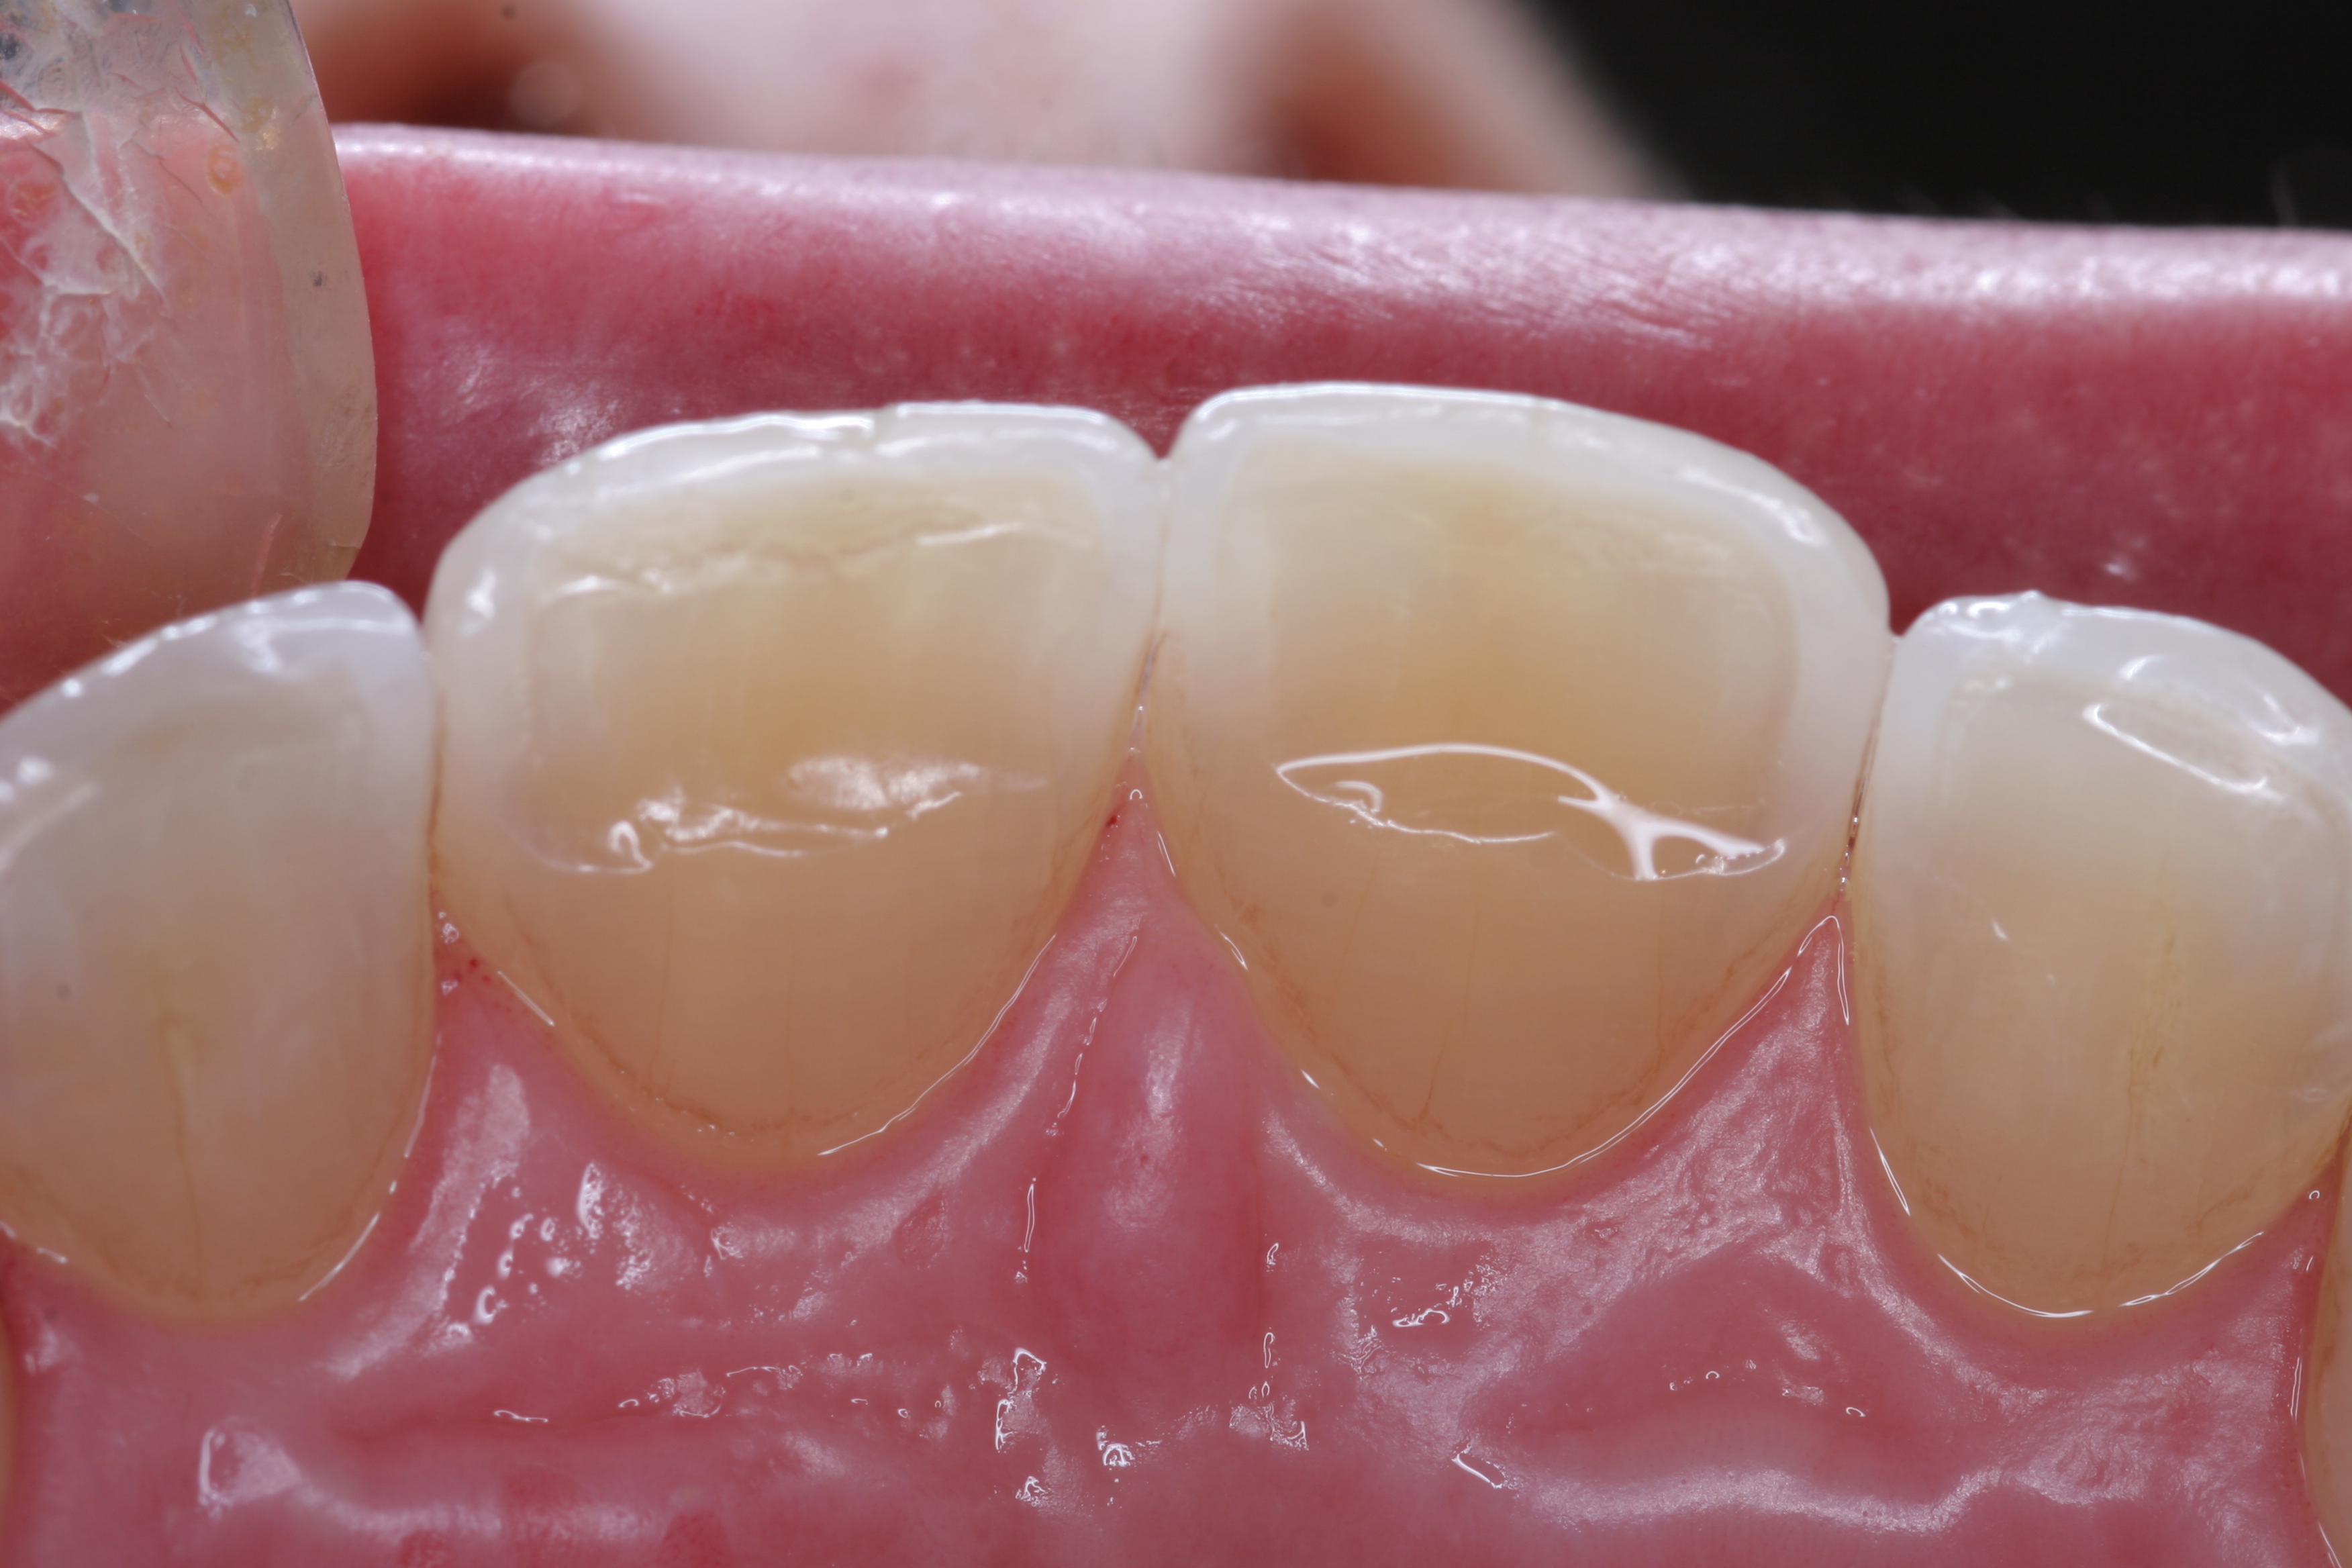

(10.) A patient presented with advanced generalized wear of her anterior teeth, and was displeased with their overall appearance because of their color and wear.

Figure 10

(11.) A patient presented with advanced generalized wear of her anterior teeth, and was displeased with their overall appearance because of their color and wear.

Figure 11

A patient presented with advanced generalized wear of her anterior teeth (Figure 10 and Figure 11). She was displeased with their overall appearance because of their color and wear (Figure 12). A complete examination was performed, revealing instability in her temporomandibular lateral poles bilaterally, sore muscles of mastication, advanced wear, a CR/MIP discrepancy, and loss of her anterior guidance due to the wear. Although the topic is beyond the scope of this article, the patient was also screened for possible sleep apnea. This included an evaluation of the Mallampati score, previous sleep therapy evaluation or treatment, snoring history, an evaluation of her neck size, her weight status, and the presence of the tonsils and their size. In every case, if this clinician suspects airway obstruction to be playing a role in tooth wear issues, the patient is referred to a sleep physician. The patient in this case displayed few apnea risk factors, and the patient’s anterior wear facets fit together like a “lock and key” pattern seen in parafunctional activity. Splint therapy was initiated to stabilize the joints and muscles. A repeatable CR position was verified through load testing. At this point diagnostic models, photographs, a CR bite record, and a facebow were taken and recorded.